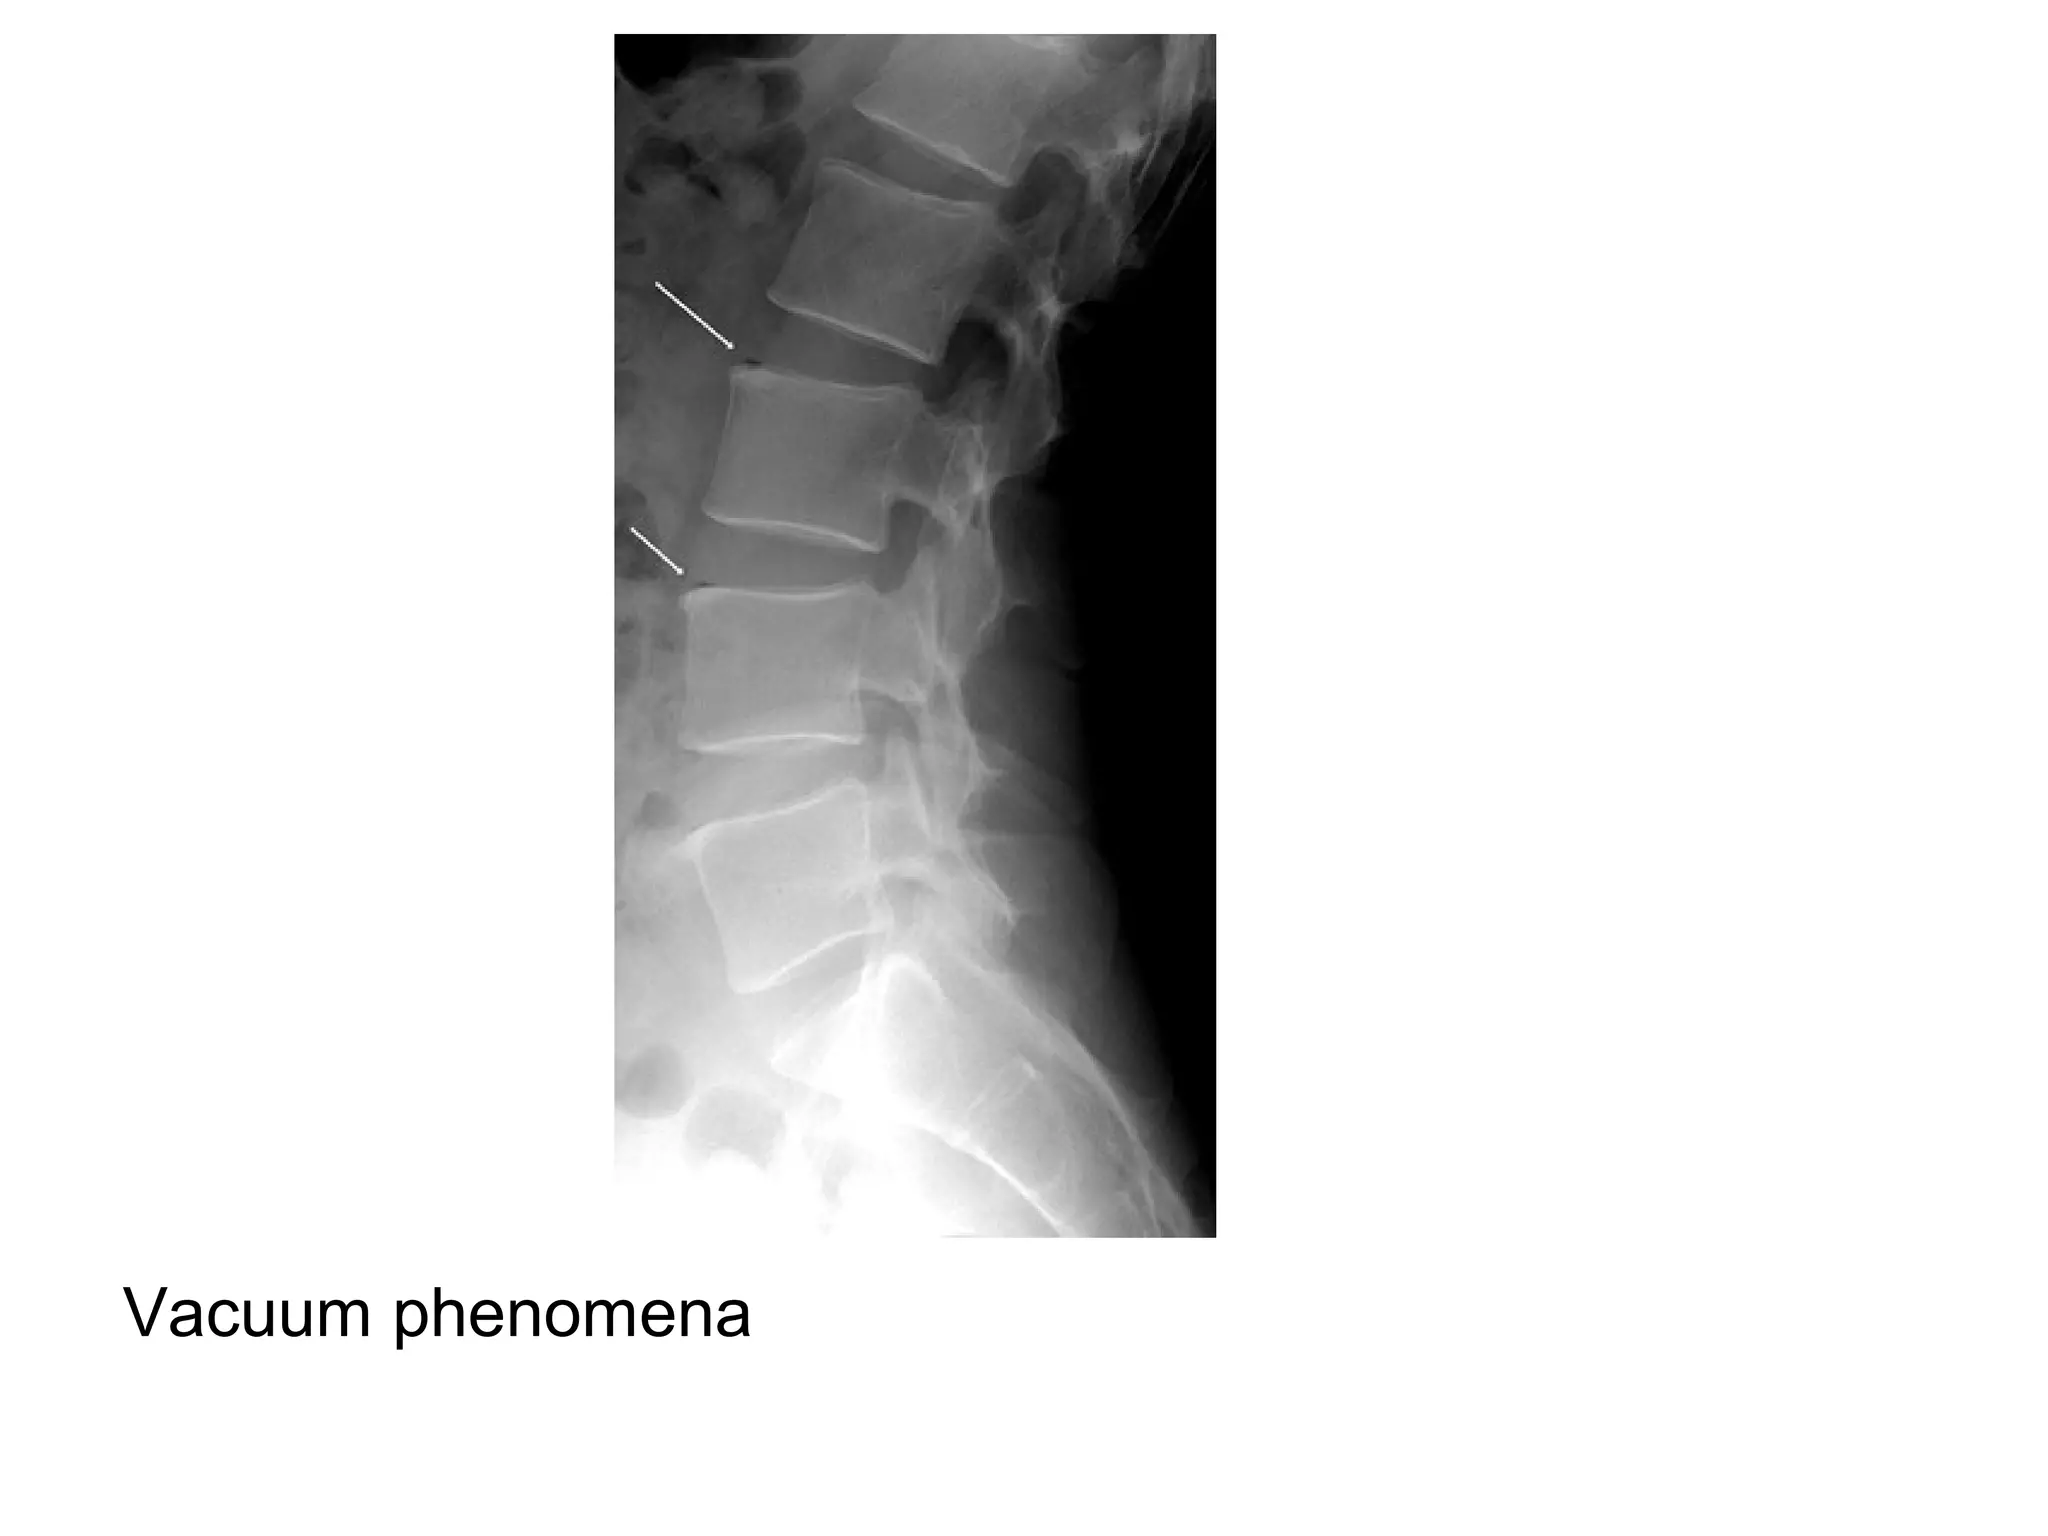

1-Plain Radiography :

-Disk space narrowing

-Vacuum phenomenon in disk space (gas in the

intervertebral disc) , pathognomonic for

degenerative disease

**N.B. :

-It is important not to confuse vacuum

phenomenon (gas in intervertebral disc) with

Kummel disease which is gas in a vertebral body

compression fracture representing

osteonecrosis

Narrowed disc space with vacuum phenomenon

Vacuum phenomena